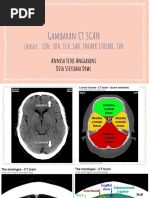

CT scan normal

 Frontal lobes (F)

 Temporal lobes (T)

 Temporal horns (panah putih)

 Fourth ventricle (4)

 Cerebellum (C)

 Pons (P)

 Suprasellar cistern (S)

 Cerebral peduncles (panah putih)

 Interpeduncular cistern (panah hitam)

 Sylvian fissures (S)

 Third ventricle (3)

 Quadrigeminal plate cistern (panah putih)

 Frontal horns of the lateral ventricles

(panah putih)

 Caudate nuclei (C)

 Occipital lobes (O)

 Lentiform nuclei (L)

 Calcified pineal gland (panah putih)

 Genus of corpus callosum (dotted white arrow)

 Lateral ventricles (L)

 Septum pellucidum (dashed white arrow)

 Parietal lobes (P)

 Occipital horn (black arrow)

 Calcified choroid plexus (solid white arrows)

Falx Cerebri

Lobus Frontalis

Fissura Sylvii

Interpeduncular cistern

Suprasellar cistern

Ambien Cistern

Quandrigeminal Cistern